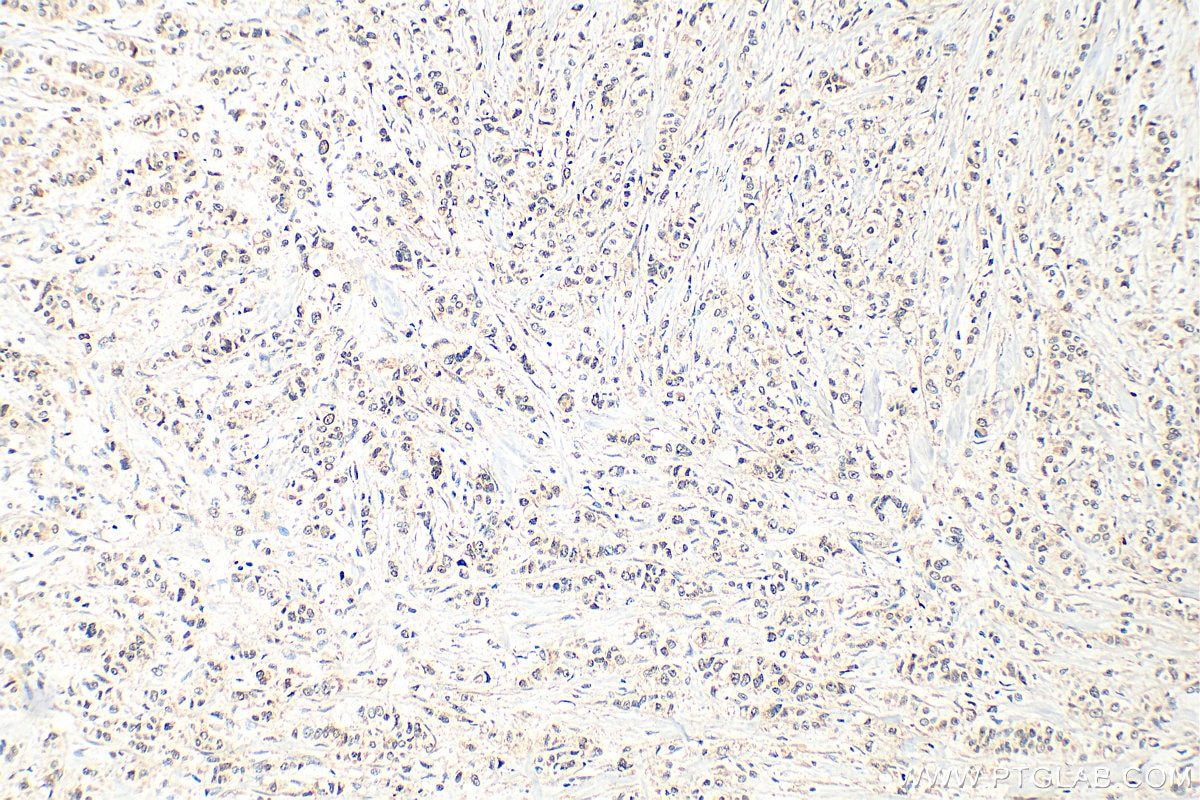

Tested Applications

| Positive IHC detected in | human breast cancer tissue Note: suggested antigen retrieval with TE buffer pH 9.0; (*) Alternatively, antigen retrieval may be performed with citrate buffer pH 6.0 |

| Immunohistochemistry (IHC) | IHC : 1:50-1:500 |

32948-1-AP targets DDX59 in WB, IHC, ELISA applications and shows reactivity with human samples.